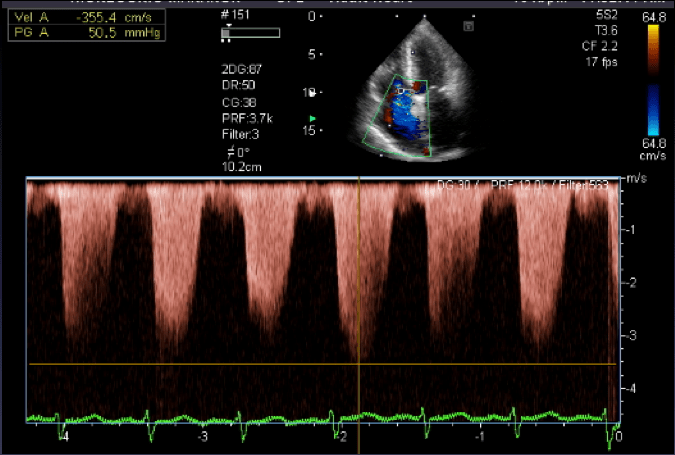

Una vez finalizado el estudio de las cavidades izquierdas, vamos a poner el Doppler color sobre la válvula tricúspide. En este caso no nos interesa tanto el llenado transvalvular como la insuficiencia que pudiera existir porque gracias a ella vamos a calcular la PSAP (Presión sistólica en arteria pulmonar) de manera no invasiva. Si observamos una regurgitación con el Doppler color, hay que alinear la barra de muestra del Doppler continuo con la dirección de la misma para obtener una buena medida de la velocidad máxima de regurgitación (figura 20). Con la fórmula PSAP = (Vmax2 x4) + RAP, pasaremos de tener una velocidad a una presión en mmHg, que de ser superior a 50 mmHg, nos hará pensar en HTP. Este punto hay que relacionarlo con la morfología de la curva espectral que obtuvimos en la válvula pulmonar (eje corto grandes vasos) y, por supuesto, con la clínica del paciente.

After completing the study of the left cavities, we will put the color Doppler on the tricuspid valve. In this case we are not interested in transvalvular filling as much as in the insufficiency that could exist because thanks to it we are going to calculate the PSAP (pulmonary artery systolic pressure) in a non-invasive way. If we observe a regurgitation with the color Doppler, it is necessary to align the sample bar of the continuous Doppler with the direction of the same to obtain a good measure of the maximum regurgitation velocity (figure 20). With the formula PSAP = (Vmax2 x4) + RAP, we will go from having a velocity to a pressure in mmHg, which if it is higher than 50 mmHg, will make us think of HTP. This point has to be related to the morphology of the spectral curve that we obtained in the pulmonary valve (short axis large vessels) and, of course, to the patient’s clinic.